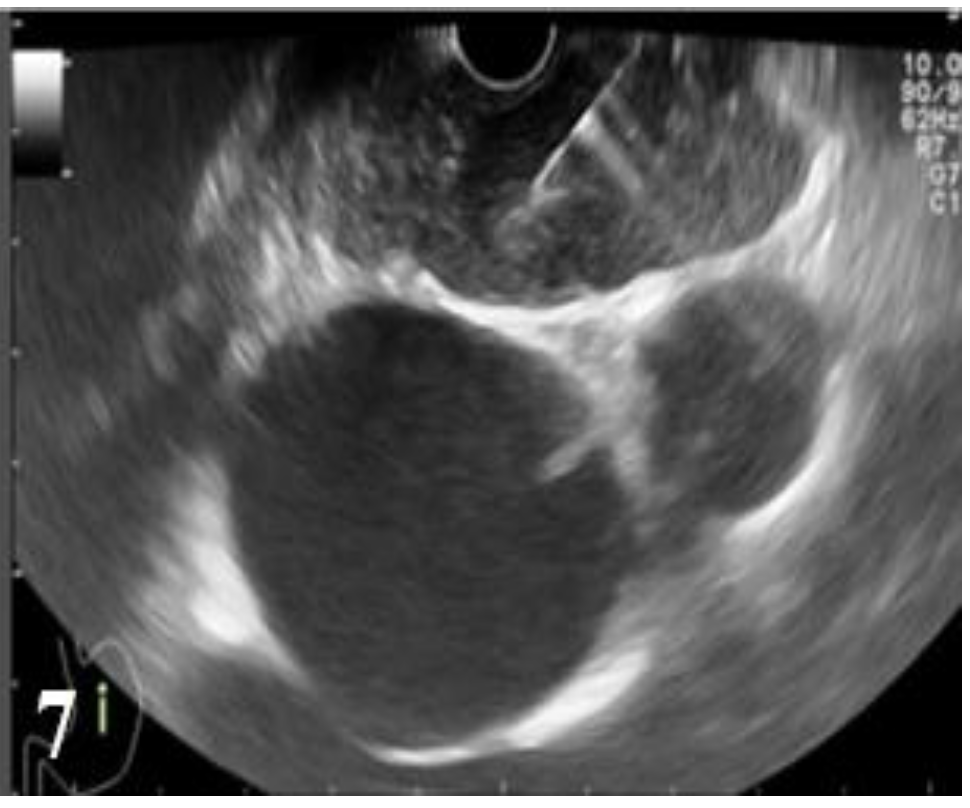

Figure 2.

Postcontrast CT, arterial phase, axial plane. Stenosing tumor of the distal esophagus and gastroesophageal junction that is tangent to the intrathoracic descending aorta and partially compresses the left pulmonary vein with no obvious signs of macroscopic invasion.